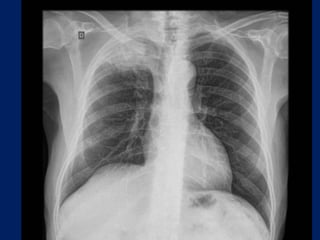

Chest radiographs may show the following:

• Pulmonary nodule, mass, or infiltrate

• Mediastinal widening

• Atelectasis

• Hilar enlargement

• Pleural effusion

Lung Cancer:

Findings on Chest X-ray

• Nodule (< 3cm) vs. Mass (>= 3cm).

– Location:

• Peripheral (Adenocarcinoma) vs.

• Central (Squamous).

– Single or multiple (metastases).

• Endobronchial obstruction.

– Atelectasis of lobe or lung.

– Pneumonia.